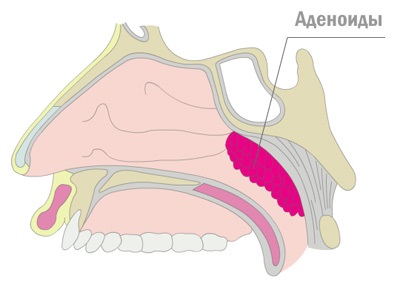

A betegség lefolyása és a klinikai tünetek okozta a hely, ahol az orrpolip találhatók. Nem található a hátsó falon az orrgarat meghatározza problémás orr légzés, hibás tárgyalásra ventilációs csövek, valamint zavar a garat.

Nasopharyngealis mandulák páros szervek, hogy tegye át a garat szájpadlása. Normális, úgy néznek ki, mint a kis fókák nyálkahártyáját. Szín mandulák körülményektől függ, és jelenléte a gyulladásos folyamat. Normális működés nem különböznek színt a környező szöveteket. Orrpolip találja magát lehetetlen, köszönhetően a nehezen helyét, így a diagnózis nélküli vizsgálatot végző orvos lehetetlen.

Három fokozata van az adenoid vegetáció, hogy pontosan meghatározzák, hogy szükség van, hogy vizsgálja meg, hogyan néz orrpolip.

Az emelkedés mértéke az orrpolip